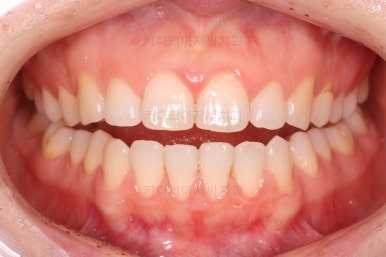

부산나비앞니교정 키다리아저씨치과에서 치료를 한 지 3개월째의 모습입니다.

굉장히 많이 가지런해 진 것을 볼 수 있어요.

그래도 여전히 나비앞니의 느낌이 남아있어서 미세한 조절을 더 하고 마무리를 하기로 했습니다.

벌써 치료 종료시의 모습입니다.

치료는 총 5개월이 걸렸네요.

일반적으로 부분교정은 6개월 전후로 치료기간이 걸리긴 하고 이번 환자분의 경우는 삐뚤어진 정도가 심한 편이 아니라서 짧게 걸린 편이었어요.

치료결과는 매우 만족하셨습니다.

삐뚤었던, V자로 꺾여있던 나비앞니치아가 가지런해졌어요.

양치질도 훨씬 편해져서 장기적으로 구강건강에도 도웅미 되실 거에요.

다시 틀어지지 말라고 앞니 안쪽에 유지장치를 부착해 주고 마무리를 했습니다.